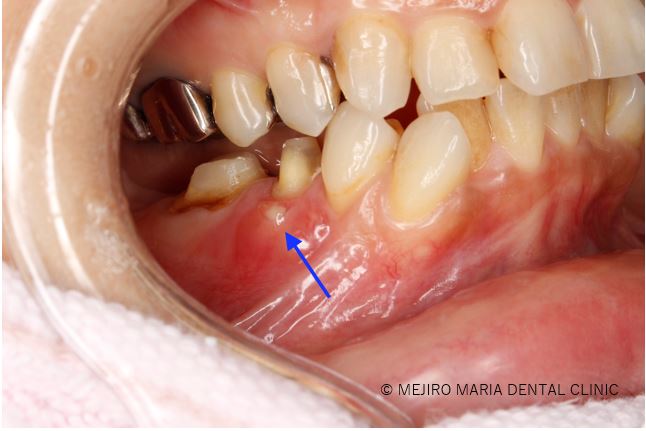

【症例】セラミック治療後に発症した根尖性歯周炎に対する歯根端切除術

【症例】歯根端切除術により抜歯を覚悟していた歯の保存に成功

【症例】根管治療だけでは治癒に至らない歯を歯根端切除術で保存

【症例】抜歯を宣告された歯を外科的根管治療「歯根端切除術」で保存(1年後経過観察追加)